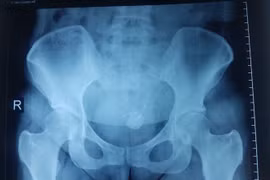

(GLO)-Lần đầu tiên trong lịch sử y học, một bàng quang người được cấy ghép hoàn chỉnh và hoạt động tốt trong cơ thể người nhận.